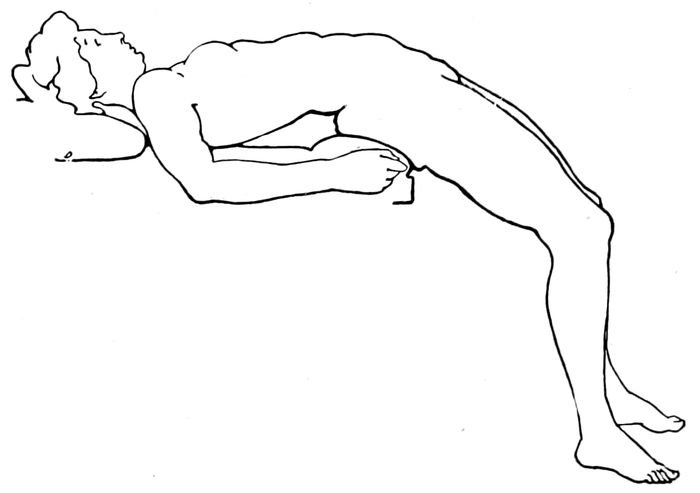

| 83. |

The Walcher position |

194 |